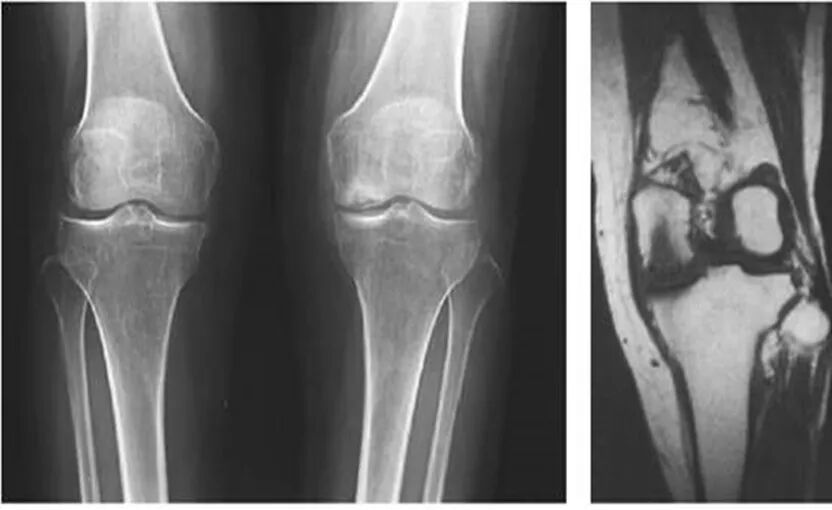

2、X线片(站立或负重位)示关节间隙变窄、软骨下骨硬化、和(或)囊性变、关节缘骨赘形成。

8、膝关节畸形改变,以膝关节内翻畸形最为常见。

1、关节间隙变窄:成人膝关节间隙为4mm,小于3mm即为关节间隙狭窄,60岁以上的老人膝关节间隙为3mm,小于2mm为关节间隙狭窄。

2、软骨下骨板硬化:软骨下骨板致密、硬化,负重软骨下骨质内可见囊性改变。

3、骨赘形成。